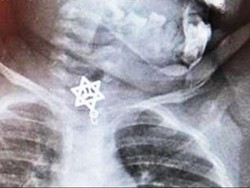

Nuraulia Hermila (13), kritis setelah terserempet Kereta Api Pangrango yang tengah melintas dari Sukabumi menuju Bogor. Saat kejadian, ia baru pulang Sanlat.